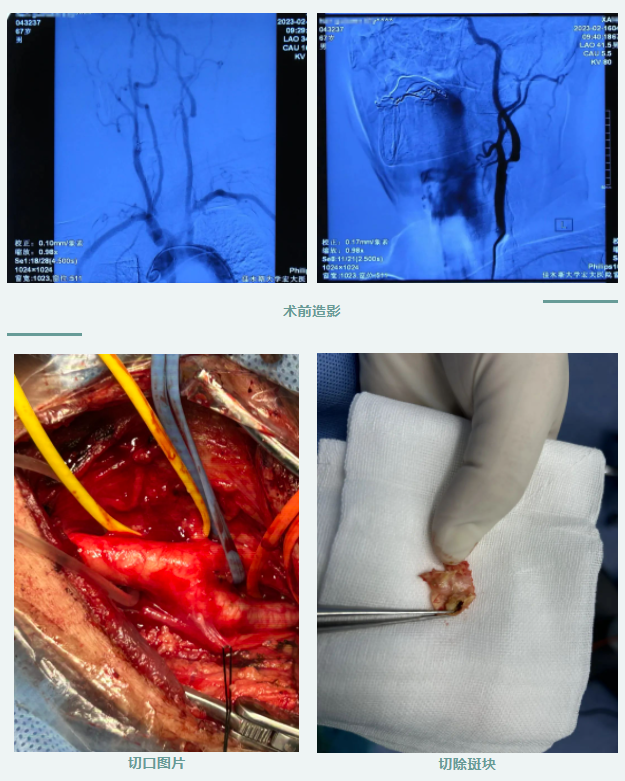

近七旬的患者劉先生,因“頭暈乏力、上肢無(wú)知覺(jué)”來(lái)到我院就診,經(jīng)雙側(cè)頸動(dòng)脈超聲檢查提示:雙側(cè)頸部動(dòng)脈粥樣硬化性斑塊形成伴局部管腔狹窄,為進(jìn)一步明確診斷,在神經(jīng)介入內(nèi)二科艾長(zhǎng)思主任的帶領(lǐng)下,又為劉先生進(jìn)行了腦血管造影檢查,最終確診為“重度左側(cè)頸內(nèi)動(dòng)脈狹窄”。陳虹院長(zhǎng)帶領(lǐng)神經(jīng)內(nèi)科介入治療團(tuán)隊(duì)對(duì)該患者進(jìn)行了會(huì)診,經(jīng)全面評(píng)估,決定為其實(shí)施“頸動(dòng)脈內(nèi)膜剝脫術(shù)”,并為患者制定了縝密的手術(shù)方案。繼而,再一次開(kāi)展了團(tuán)隊(duì)醫(yī)護(hù)人員專項(xiàng)救治培訓(xùn),經(jīng)過(guò)與患者及家屬有效溝通,確定了治療方案。

術(shù)前,醫(yī)護(hù)人員對(duì)患者進(jìn)行詳細(xì)檢查,結(jié)合患者斑塊形狀以及周圍組織關(guān)系等,積極做好各項(xiàng)準(zhǔn)備工作;術(shù)中,艾長(zhǎng)思主任團(tuán)隊(duì)在麻醉科和手術(shù)室的密切配合下,為患者進(jìn)行頸動(dòng)脈內(nèi)膜剝脫手術(shù),取左側(cè)胸鎖乳突肌前緣斜切口,長(zhǎng)約7cm,上段至下頜角水平上方2cm,打開(kāi)頸動(dòng)脈鞘,顯露頸總動(dòng)脈分叉部及頸內(nèi)、頸外動(dòng)脈分支,可見(jiàn)頸內(nèi)動(dòng)脈起始部斑塊。鈍性分離切除頸總遠(yuǎn)端及頸內(nèi)、頸外動(dòng)脈近端內(nèi)膜斑塊,肝素鹽水沖洗,縫合動(dòng)脈切口,依次開(kāi)放頸外、頸總及頸內(nèi)動(dòng)脈血流。此次手術(shù)歷時(shí)1小時(shí),成功剝脫了患者頸動(dòng)脈斑塊,使病變的頸動(dòng)脈重新恢復(fù)暢通與活力。